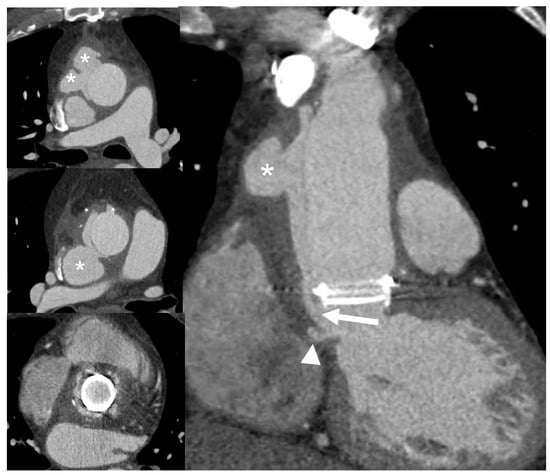

7.3. Role of CCTA in Diagnosing CIED-IE and Local Complications

| CIED-IE | Useful to assess intracardiac lead segments. TTE can be integrated by ultrasound evaluation of device pocket, to assessing inflamation or fluid collection. | Limited role in the assessment of unexplorable lead segments. Differential diagnosis of vegetation vs. lead fibrosis/thrombi can be challenging. | Possibility to combine the CT assessment of generator pocket. | Blooming and beam hardening artefacts. Poor sensitivity in detecting vegetations on leads. | Very high sensitivity and specificity for generator/pocket and extracardiac or extravascular lead infection. | Low sensitivity for small vegetations along the leads. | Good sensitivity and specificity for generator/pocket and extracardiac or extravascular lead infection. | Limited diagnostic sensitivity for intracardiac and intravascular lead infection. | Image quality severely hampered by susceptibility artifacts from lead and device. Limited to patients with MRI conditional devices and with numerous precautions. | |